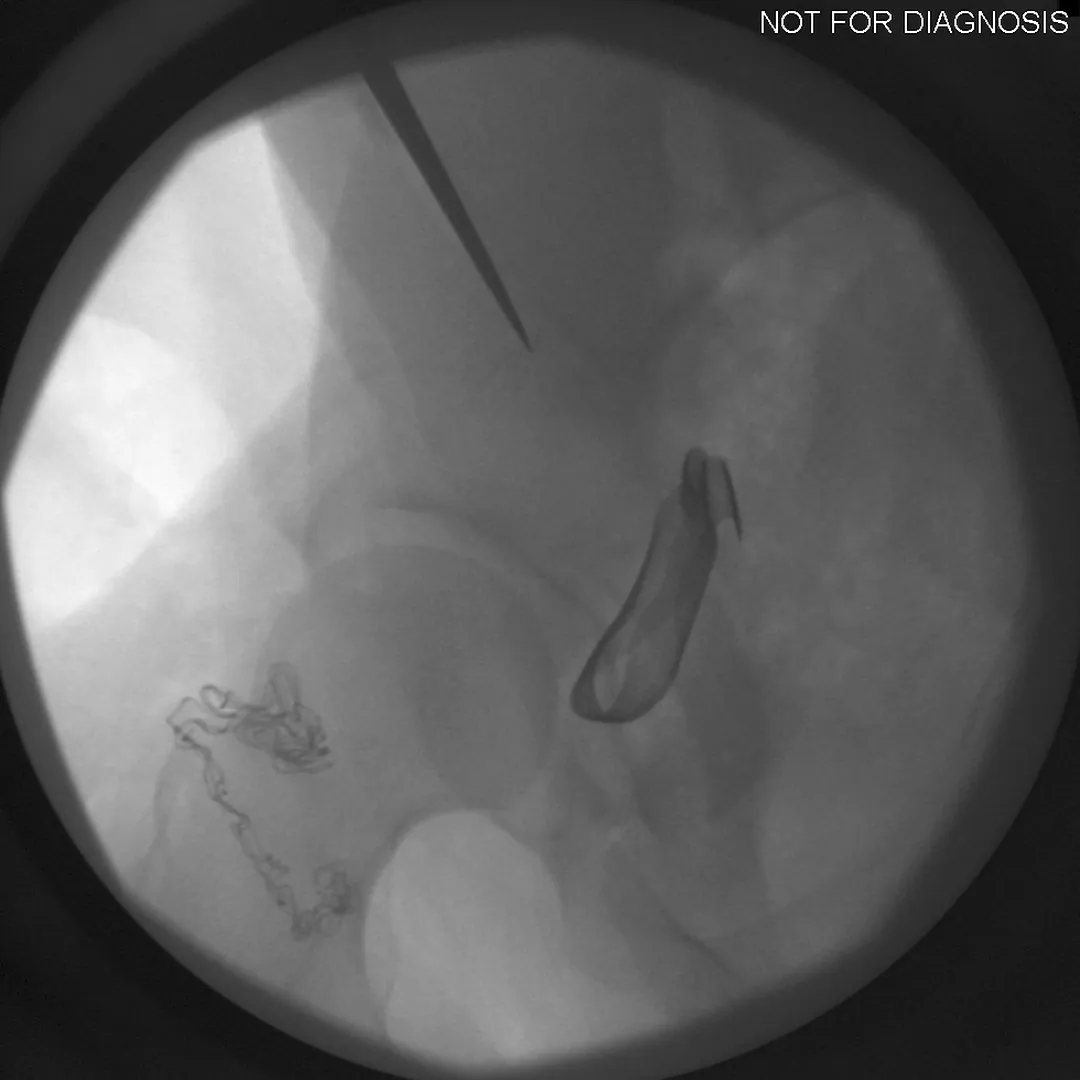

The Surgery

• PAO surgery typically takes 2-4 hours

• It is performed under general anesthesia

• Several controlled bone cuts are made around the hip socket

• The socket is repositioned and fixed with screws

• The hip joint itself is preserved